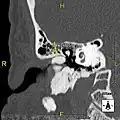

Normal ear canal

Exostosis in ear canal